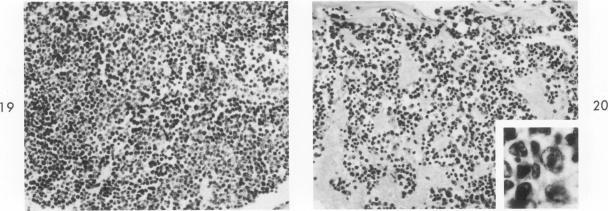

During studies on the effect of murine cytomegalovirus on the developing retina, virus was inoculated into the eyes of newborn Swiss mice, and the animals were sacrificed at various times thereafter. Controls consisted of mice inoculated with ultraviolet-inactivated murine cytomegalovirus and uninjected mice. Marked lymphoid cell necrosis, thymic atrophy, pronounced growth retardation, bacteremia, and death occurred in the animals inoculated with live virus. this virus-induced injury resulted in a marked depletion of lymphocytes in the subcapsular and cortical areas of the thymus as well as in the spleen, lymph nodes, and Peyer's patches. Areas of necrosis with viral inclusions were present at the site of inoculation and in various other organs including the spleen and bone marrow. Since growth retardation has been associated with thymic atrophy due to other causes, the observed abnormal physical development in the present study was interpreted as a sequel to the thymic injury. An implication of this study is that some human infants with concomitant immune deficiency and viral infection may have a primary viral disease with resultant secondary lymphoid tissue alterations, rather than a thymic disorder with a subsequent viral infection.